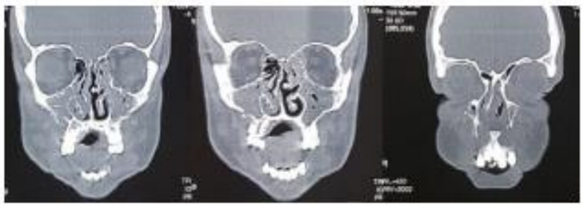

M.A.,32 anos, é atendido no Pronto Atendimento do Hospital Regional, vítima de colisão automoto. Ao exame físico: Desorientado, Pupilas Isocóricas e com reflexos pupilares preservados, edema de face, múltiplas escoriações, hematomas na região frontal e malar bilateral, afundamento do dorso nasal, epistaxe bilateral, ao exame da cavidade oral: fratura dos incisivos centrais superiores e presença de mobilidade da maxila. A partir dessas informações e após a análise do seguinte exame de imagem abaixo, assinale a alternativa que contém o diagnóstico: